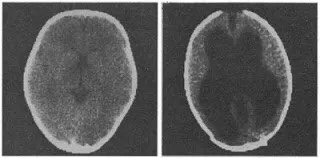

《柳叶刀》曾在2007发布过这样一个案例:一名44岁的法国男子左腿有点问题,他就找人看,顺便对大脑做了核磁共振扫描,结果发现他的脑里都是积水,脑组织已经被挤得只剩下薄薄的一层。和正常人相比,他的大脑“几乎不存在”。经过测试,他的智商有75,和阿甘差不多。他很早就结了婚,还生了两个孩子,生活很美满,可以说没受到什么影响。如果不是因为左腿疼,他可能永远也不会发现自己其实“没脑子”。

左边是该男子的大脑;右边是正常人的大脑。中间黑色部分就是积水